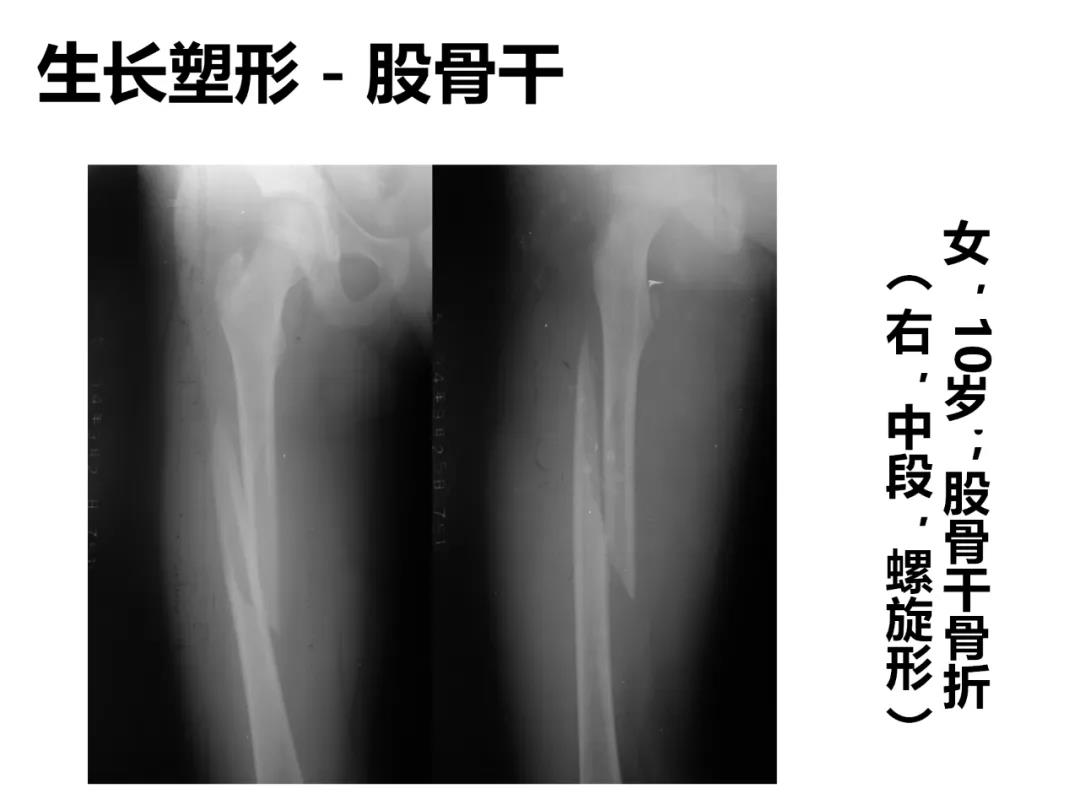

小儿骨科X线片汇总,临床读片宝典!